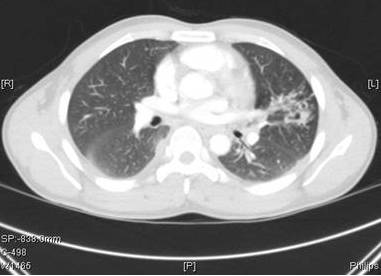

图1就诊前4个月的胸部CT

图2: 出现症状是的胸部CT(进行4个月的抗结核治疗)

肺结核是不可能有几次AFB 培养转阴。经纤维支气管镜肺泡灌洗也有几次阴性的AFB染色和培养。此外,虽然进行多种抗结核药物治疗,但空洞恶化。急性支气管炎不是肺空洞的常见原因。

与肺结核相反,肺吸虫病很少伴有啰音或偶发呼吸音。急性期(侵袭和转移)可表现为腹泻、腹痛、发热、咳嗽、荨麻疹、肝脾肿大、肺部异常,外周和BAL样本中嗜酸性粒细胞增多。肺吸虫侵袭和迁移的时期的急性期包括腹痛、腹泻和荨麻疹,随后大约1到2周后出现发热、胸膜炎性胸痛、咳嗽和/或呼吸困难。在慢性期,肺部症状较轻,并有咳嗽、咯血痰,痰液变色,和胸片异常。影像学异常包括胸腔积液、局灶性纤维化胸膜增厚、胸膜下结节,实质性团块,迁移性浸润、空洞性病变、印戒征,少见气液平。最常见的有症状的肺外部位是中枢神经系统。大脑中的吸虫可导致剧烈头痛、头晕、视力障碍。慢性感染可表现为癫痫发作、瘫痪或精神发育迟滞。